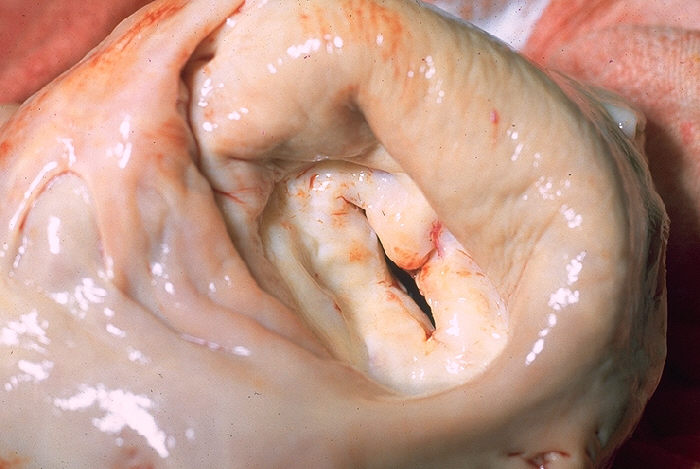

The mitral valve is the most affected cardiac valve.

Small vegetations accrue on the valve along the lines of closure that result in mitral regurgitation.

Chronic rheumatic heart disease develops when rheumatic fever-related valve scarring leads to stenosis with the classic fish-mouth appearance.

In chronic rheumatic heart disease, the chordae tendineae and cusps thicken as a result of the mitral valve being involved almost always.

The narrowing of the mitral valve orifice is known as mitral stenosis.

Mitral stenosis is associated with persistent rheumatic valve disease.